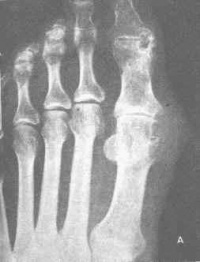

痛风X线检查[编辑 | 编辑源代码]

骨关节为痛风患者常见的受累部位。骨骼内还有大量钙盐,因而密度较高并与周围软组织形成良好对比。因此,病变易为X线检查所显示。普通X线摄片和X线数字摄影(CR或DR)简单易行,费用较低,可显示四肢骨关节较为明显的骨质改变、关节间隙和骨性关节面异常及关节肿胀。X线平片通常作为了解痛风病人有无骨关节受累的首选影像学检查方法。

X线检查包括常规检查和特殊检查。常规检查应摄取检查部位的正侧位片,骨骼病变摄片范围应包括一个相邻的关节。特殊检查主要有放大摄影、体层摄影和软组织靶摄影。放大摄影系利用小焦点的X线束自焦点向远处不断扩大的原理,使检查部位与胶片或X线感应板之间保持较大距离,从而获得放大图像,以便更好地观察骨骼的细微结构。体层摄影和软组织钼靶摄影正逐渐为CT检查所取代,现已很少应用。